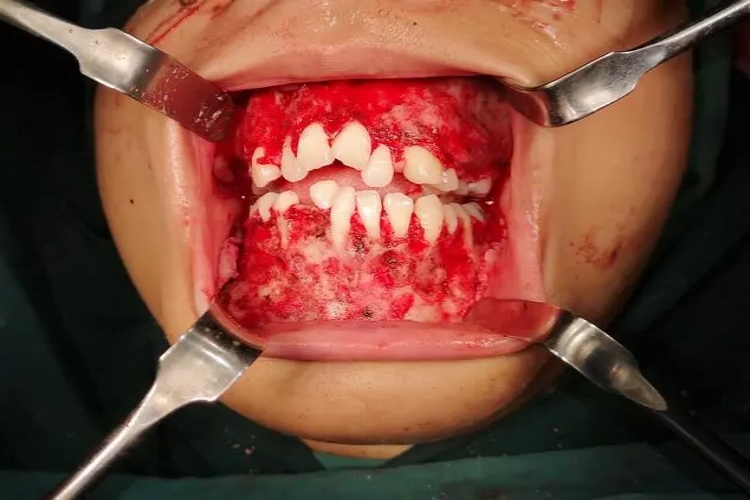

巨颌症可导致牙齿发育异常,出现乳牙过早剥脱、恒牙移位等情况,表现为牙齿双排畸形分布,牙齿间隙变宽,严重时甚至导致颌骨病变,患者可伴有面颊肿胀等表现。